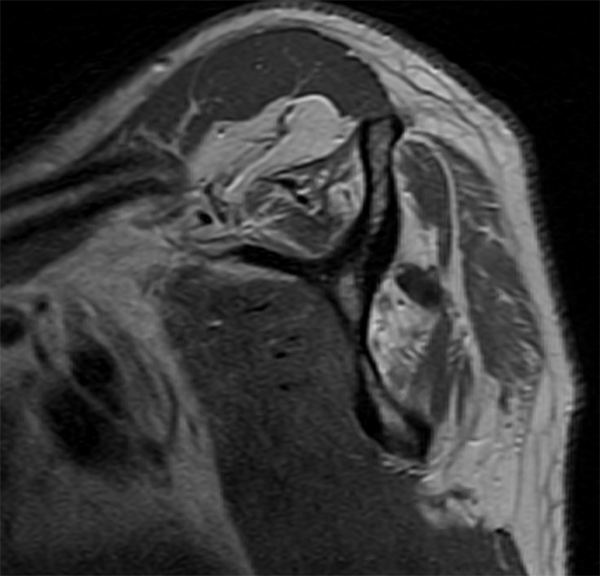

A laborer in his 50s came to my office today with complaints of left shoulder pain. He had injured it a year ago in a fall and had initially seen another provider who gave him a cortisone shot. He had been doing reasonably well but continued to have pain and weakness and tried to work through it . He eventually saw his primary doctor and got an MRI before being sent to me, again almost a year later. On exam the man was very weak when I tested his rotator cuff. On MRI the patient had a massive rotator cuff tear with development of atrophy (fatty infiltration) of his rotator cuff muscles. Whereas we probably could have fixed his rotator cuff a year ago and he would have likely been healed, the tear was now no longer repairable. Thankfully, I am able to offer him a recently developed reconstructive procedure called a lower trapezius transfer, which has been very successful for treating these types of patients in salvage situations.